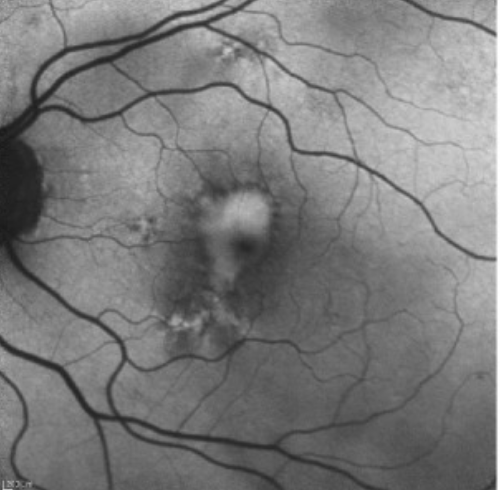

• Fluorescein Angiography to rule out leakage

Rocha Bastos R, Ferreira CS, Brandão E, Falcão-Reis F, Carneiro ÂM. Multimodal Image Analysis in Acquired Vitelliform Lesions and Adult-Onset Foveomacular Vitelliform Dystrophy. J Ophthalmol. 2016;2016:6037537. doi:10.1155/2016/6037537 (image cropped)

Genetic testing: BEST1 mutation

Arden Ratio: 1.50

• Adult Foveomacular Vitelliform Retinal Dystrophy, OU